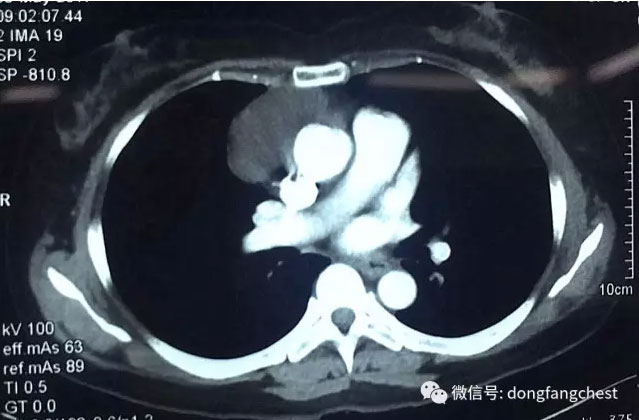

淮南市本地患者张女士今年57岁,2年前体检时发现前纵隔肿物,自从发现胸腔内的长了肿物后,张女士倍感压力,经常觉得各种不适。今年4月,张女士入院再次复查CT发现,胸腔内肿物较之前明显增大,这更让张女士和她的家人十分担心,甚至寝食难安。

经多家医院就诊咨询后,张女士选择入住东方总院胸外科进行治疗。经过术前详细的检查和针对张女士“糖尿病、高血压病”的调整准备后,以朱胜、王鸿主任为首的胸心外科团队为张女士安排了“单孔胸腔镜纵隔肿物切除”手术。为最大程度减少患者的损伤以及切口的美观,主刀医师王鸿主任仅在2cm长的小切口下就成功完整切除了约6cm大小的纵隔肿瘤,手术过程仅耗时半个多小时,手术几乎没有出血。

据东方医院集团总院胸心外科王鸿主任介绍,张女士的纵隔肿瘤贴在纵隔大血管旁边生长,手术切除具有较大风险。传统手术治疗需要取15cm以上的大切口开胸切除肿瘤,手术创伤大,患者术后恢复慢。近10余年来,经过不断的探索、实践和发展,胸腔镜微创手术技术已经成为胸外科疾病的主要治疗手段。单孔胸腔镜手术技术是胸腔镜微创手术技术进一步发展的产物,目前已广泛应用于胸外科疾病的诊治:如胸外伤、气胸、胸膜及纵隔淋巴结的活检、肺局部切除、肺叶切除、肺段切除、纵隔肿瘤切除等。与传统胸腔镜手术技术相比,单孔胸腔镜手术切口设计取消了腋后线切口及腋中线观察孔切口,所有操作器械包括胸腔镜镜体均由一个3~5cm长的切口内进出,因此损伤更小,该切口选择部位为胸壁肌肉最薄弱的位置,术后疼痛更轻,对患者感觉和运动影响也更小。由于切口选择在相对隐匿的部位,如腋窝和乳房下缘,从而使得切口更加美观,也改善了手术对患者生理及心理上的影响。在应用过程中发现,对于心肺功能相对差的患者,单孔胸腔镜手术也可以降低手术的风险。